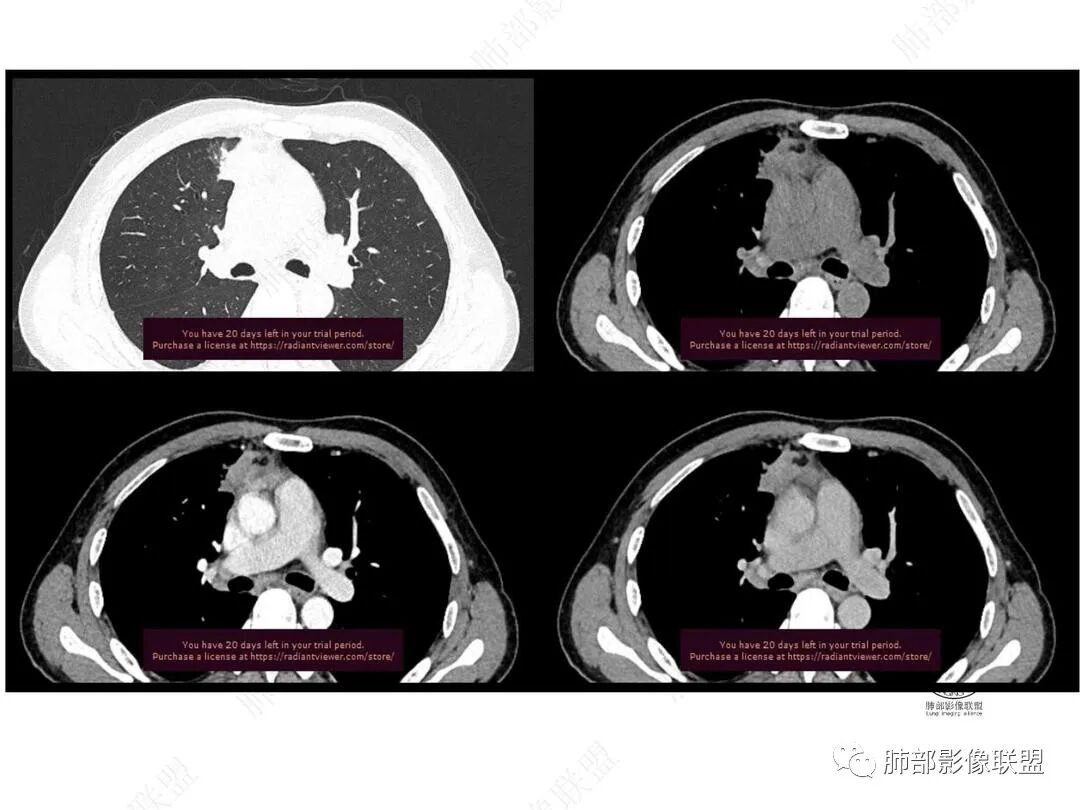

平扫图像

增强图像

右肺上叶前段纵隔旁见团块状影,边缘毛糙,部分直边,支气管进入,管壁增厚,密度均匀,明显强化。考虑炎性病变。纵隔胸膜似有栽桩,腺癌待排。

右肺上叶前段团块影,边缘毛糙,有卫星灶及小空洞,考虑结核。

中年男性,慢性发热3月,白细胞总数及crp升高,右肺上叶实变影,边缘平直为主,似乎均匀强化,血管进入后截断,考虑血管相关性曲霉感染?

中年男性,前纵膈旁团块,边缘平直,周围可见模糊的磨玻璃影,相邻支气管壁增厚,部分支气管进入病灶后阻塞,增强病灶渐进性强化,肝右叶见边缘不清的低密度影,增强渐进性强化。结合实验室检查,总体考虑炎性病变,自免性炎症?血管炎?

中年男性,右前纵隔旁不规则实变影,局部支气管进入后截断,病灶渐进性强化。肝脏右叶低密度灶,边界不清,呈明显渐进性强化。IMT?

右肺上叶纵膈旁团片,边缘毛糙,平直为主,其内见空洞,周围卫星灶,支气管进入阻塞,渐进强化,肝右叶低密度影,边界不清,渐进强化,考虑炎性病变,结核?

男,49,低热3月。胸部CT:右肺上叶前段纵隔旁见团片影,部分边缘毛糙,部分平直、内收,邻近卫星灶、晕征,重建L征?支气管管壁增厚、进入后堵塞;纵隔可见肿大淋巴结;病灶密度较均匀,中度强化。肝脏片状低密度影,边缘模糊。考虑炎性病变,PC?TB?鉴别腺癌。